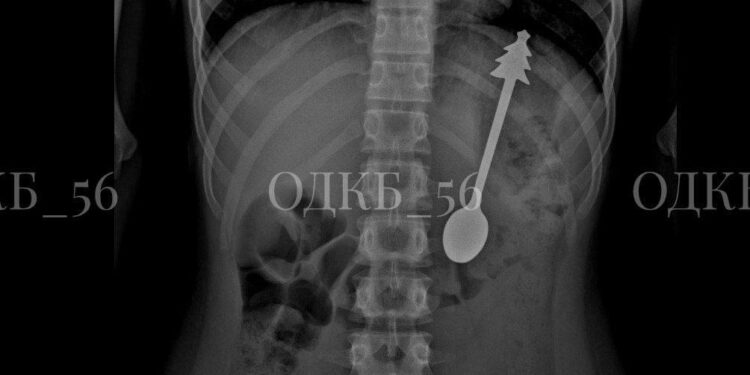

Ребёнок проглотил ложку длиной 14 сантиметров, сообщает Ult.kz со ссылкой на Telegram-канал «Новости из Кремля».

В Москве бригада скорой помощи доставила в больницу ребёнка с жалобой на попадание постороннего предмета в пищеварительные пути. При обследовании было установлено, что ложка застряла в желудке.